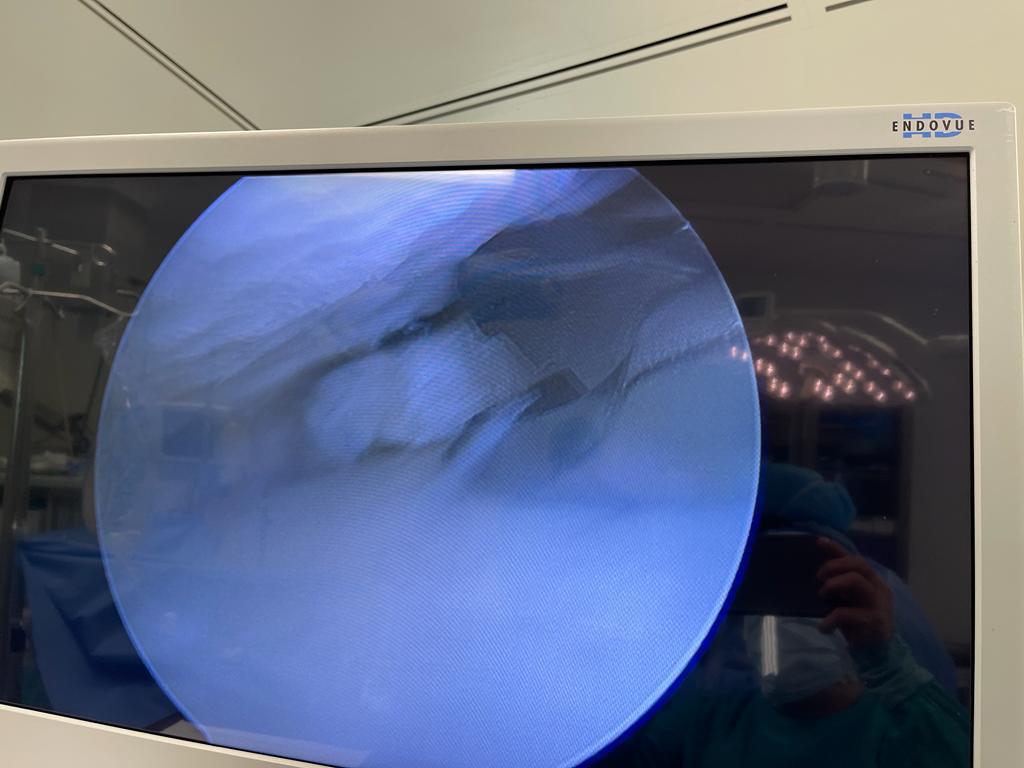

2. Discectomía Lumbar

¿Qué es?

Cirugía mínimamente invasiva para eliminar una hernia discal lumbar que causa dolor irradiado (ciática), debilidad o adormecimiento.